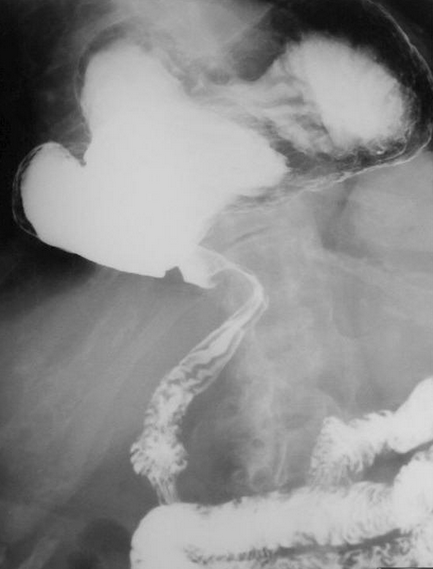

Different views of a double contrast-enhanced CT scan showing a left diaphragmatic hernia with an acute dilated stomach (Courtesy Dr. V. Penopoulos)